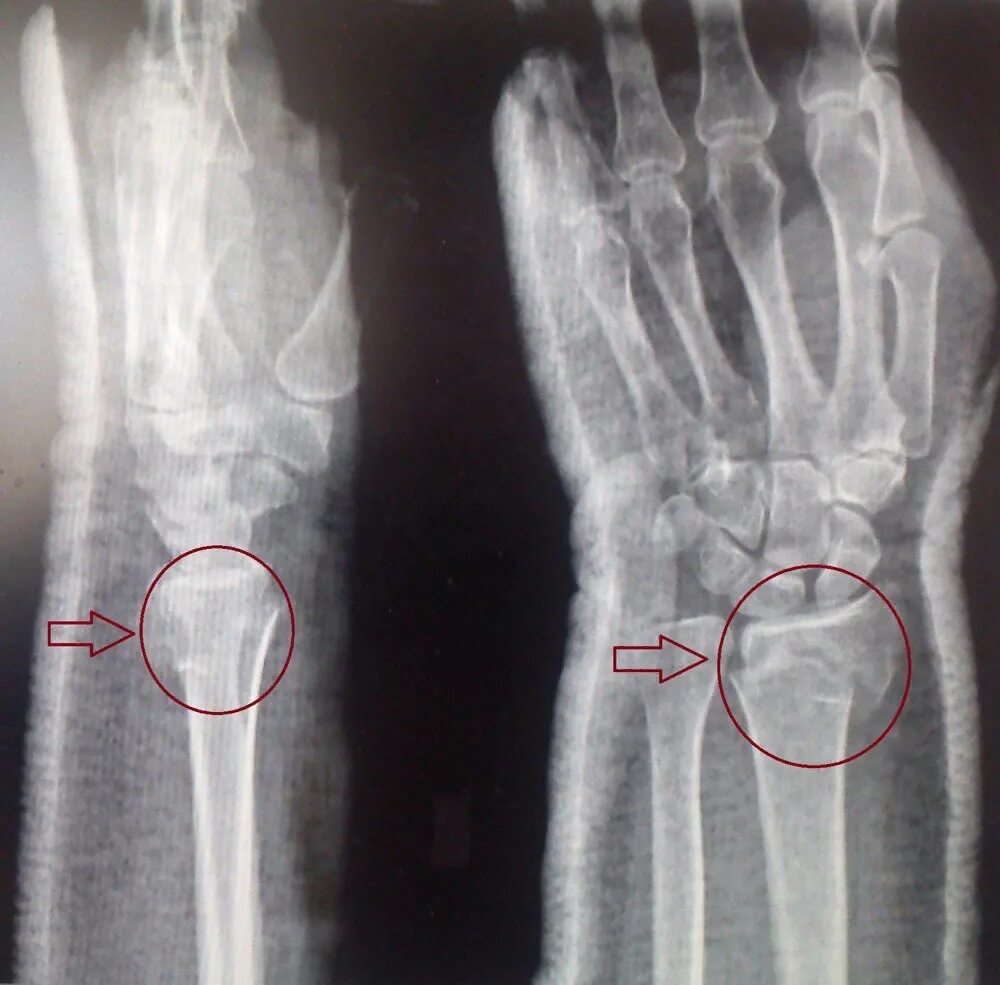

Срослась п и ж